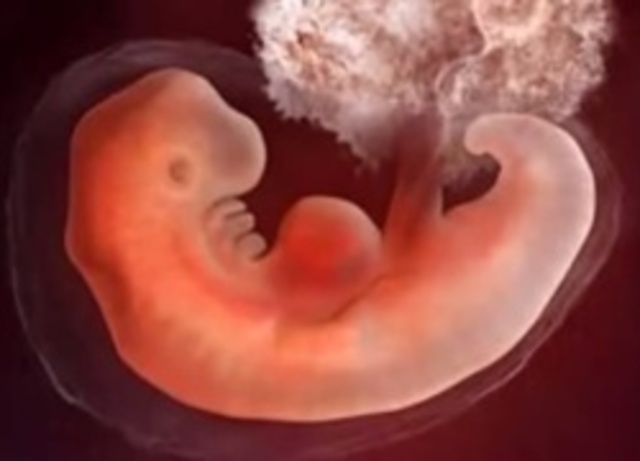

Se le llama embrionaria y comprende el perido desde la cuarta semana hasta la octava semana del desarrollo. El embrión adquiere su forma casi definitiva y desarroolla los esbozos de la mayor parte de sus órganos.Por este motivo el embrión es más sensible a las drogas u otros agentes que pueden ccausarle mal formacionescongénitas congénitas.

• 4 SEMANA

4 SEMANA

el embrión mide 4mm de longitud; ésta se mide desde el extremo de la cabeza hasta el talón. Cada día la longitud aumenta 1mm hasta el día 55 de gestación. Después crece 1,5mm diario. Comienzan los esbozos de las extremidades, la boca y las mandíbulas son visibles.